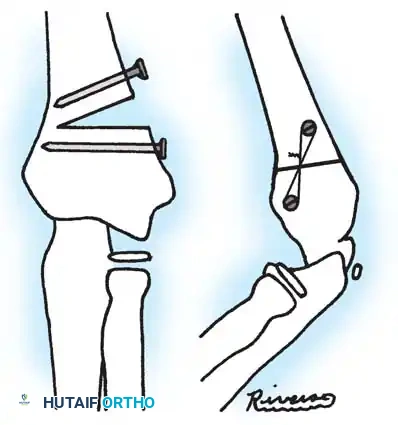

Fig. 33-44 A-D, Reduction of radial head by leverage method and retrograde intramedullary pinning with Kirschner wire.

- Fixation: Internal fixation is strictly required; periosteal sutures alone are inadequate. Oblique pins across the fracture are preferred.

Surgical Warning: Avoid transcapitellar (transarticular) wires if possible. While technically easier to insert, they carry a high risk of intraarticular breakage and septic arthritis. Merchan and Fowles both reported significant hardware failure rates with transarticular pinning.